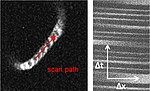

We are interested in intercellular connections, especially in those that involve endothelial cells, and in the effects of endothelial dysfunction on related brain functions. For this purpose we are using state-of-the-art technologies like two-photon microscopy, tissue-specific knockout animal models, and virus-mediated gene transfer.